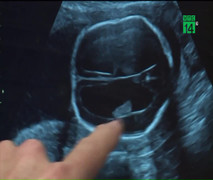

Clip: Đưa thai nhi 19 tuần tuổi ra ngoài phẫu thuật rồi trả lại bụng mẹ ngoạn mục

Đưa một thai nhi 19 tuần tuổi ra khỏi bụng mẹ, tiến hành làm phẫu thuật và sau đó đưa bé trở lại bụng mẹ, có lẽ nhiều người đang nghĩ, đây là một câu chuyện hoang tưởng, chỉ xuất hiện trên phim ảnh.